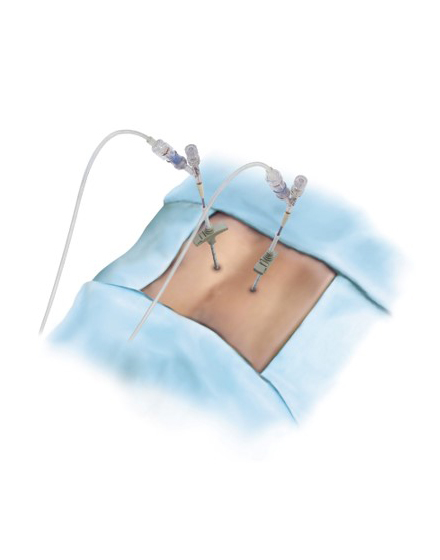

経皮的椎体形成術 BKP(ビーケーピー)

適応となる疾患:骨粗鬆症性椎体骨折、転移性脊椎腫瘍

骨粗鬆症による背骨の骨折や転移性脊椎腫瘍(がんの背骨への転移)による病的骨折に対して世界中で行われている低侵襲な手術法です。日本では2011年に保険適用になり行われています。全身麻酔をして背中の約5mmの傷2カ所から細い針を骨折椎体に挿入します。その針を介して風船(Balloon)を骨折椎体内に設置し、ゆっくりと潰れた骨を整復・復元します。整復後に除去した風船のスペースに骨セメントを注入して、骨折を人工的に接合します。手術は約1時間程度で、手術直後から痛みが軽減することが多く、翌日より起立・歩行を開始します。入院期間は通常約3~7日程度になります。